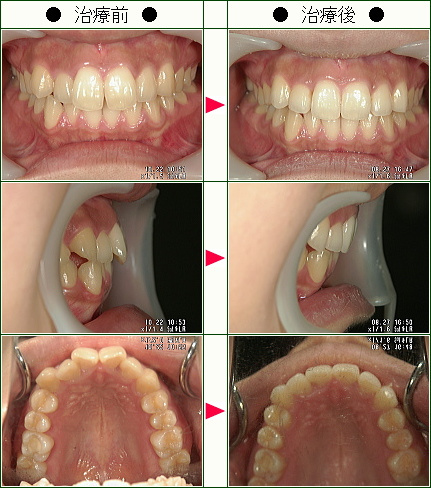

☆歯のデコボコ矯正症例(S.M.様 22歳 女性)